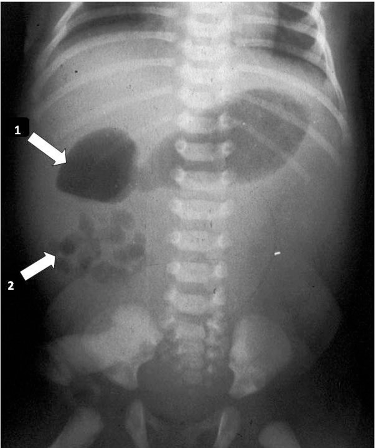

복부 X선: 위장과 십이지장에는 가스가 있고, 나머지 창자에는 가스가 없음

표준 진단: 상부위장관 조영술(UGI series)로 십이지장과 공장의 위치 확인

→ 십이지장, 공장 연결부가 중심선의 우측에 존재, 소장은 복강 우측에, 대장은 좌측에 존재